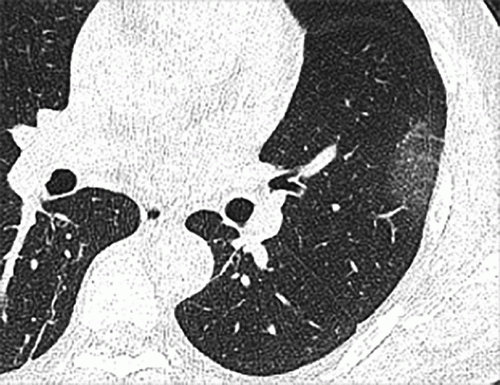

Chest CT findings of pediatric patients with COVID-19 on transaxial images. Male, 2 months old, 2 days after symptom onset. Patchy ground-glass opacities GGO in the right lower lobe. Image courtesy of Radiology: Cardiothoracic Imaging

April 6, 2020 — Children and teenagers with COVID-19 showed distinctive clinical and computed tomography (CT) findings, according to a new study published today in Radiology: Cardiothoracic Imaging. Compared to adults, pediatric patients generally had milder clinical symptoms, fewer positive CTs, and less extensive involvement on imaging. However, bronchial wall thickening was relatively more frequent on CT images from pediatric patients with COVID-19 in comparison with adults.